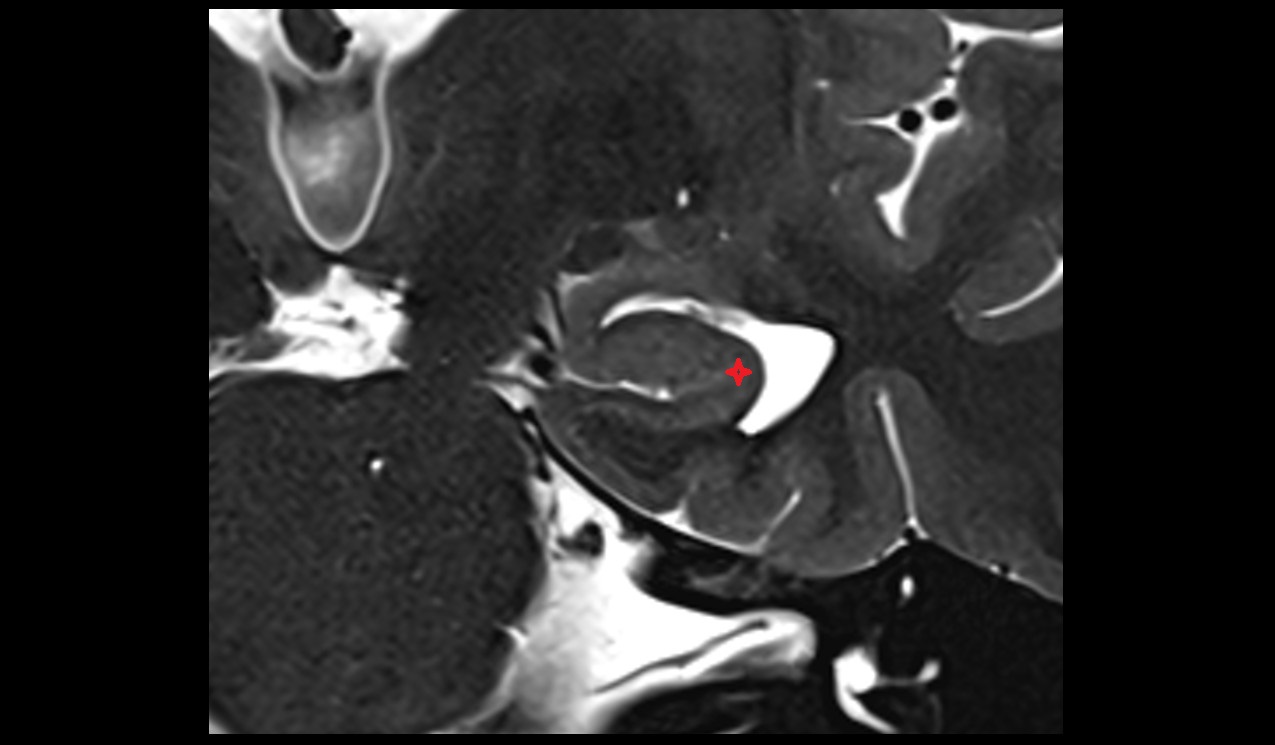

- Temporomandibular joint

- Articular disc of temporomandibular joint

- Articular eminence

- Mandibular condyle

- Mandibular fossa